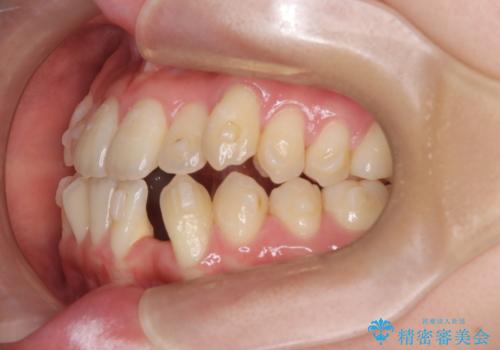

診査の結果、すでに下顎前歯の抜歯が行われていましたが、マウスピースの適合が著しく悪くなっており、歯が計画通りに動いていない状態でした。また、歯を支える骨の厚みや歯肉の薄さを考慮すると、このままマウスピースによる傾斜移動を続けるのは歯肉退縮(歯茎が下がること)のリスクが非常に高いと判断。

安全かつ確実に抜歯スペースを閉じ、咬み合わせを完成させるため、マウスピースから**ワイヤー矯正(マルチブラケット装置)**へ切り替えるリカバリープランを提案しました。